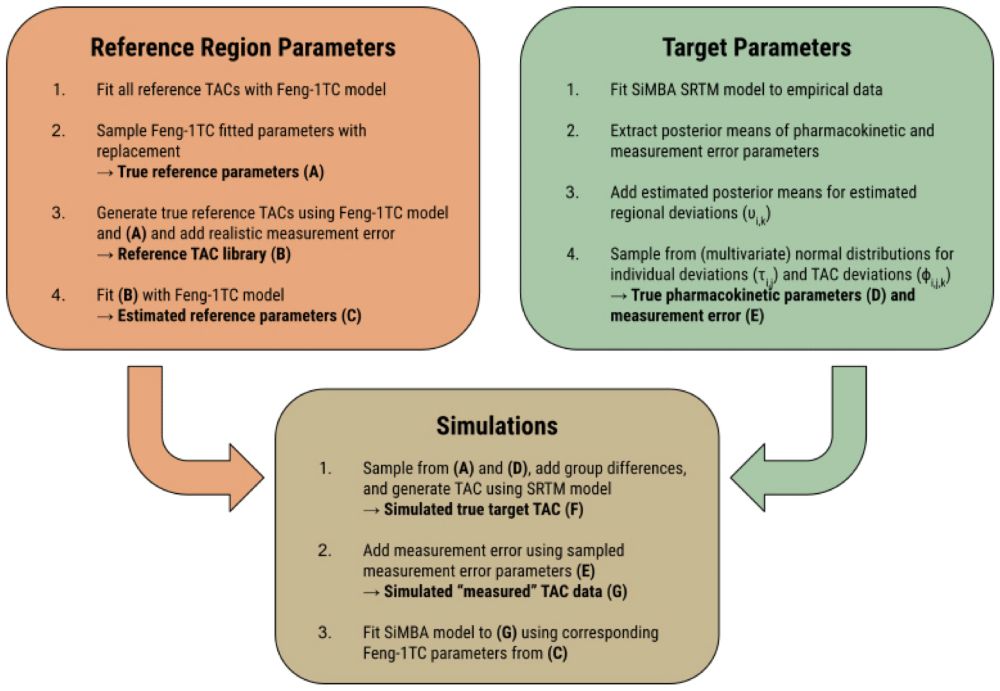

A reference tissue implementation of Simultaneous Multifactor Bayesian Analysis (SiMBA) of PET time activity curve data

doi.org/10.1162/IMAG...

A reference tissue implementation of Simultaneous Multifactor Bayesian Analysis (SiMBA) of PET time activity curve data

doi.org/10.1162/IMAG...